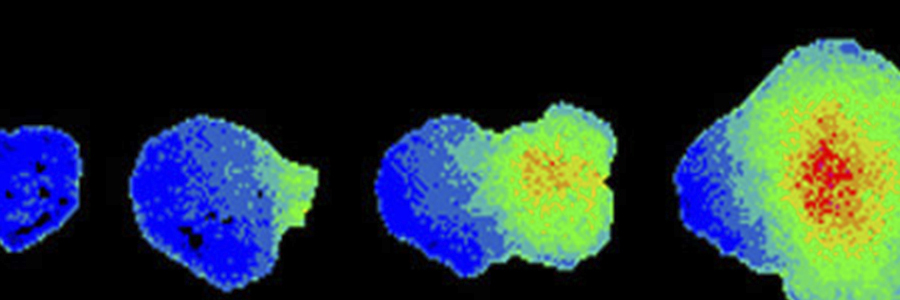

The research, carried out at the Babraham Institute, an institute of the BBSRC, investigated whether acute radiofrequency radiation emitted by mobile phones caused changes in calcium ions inside cells from the brain and blood vessels. A technique known as 'fluorescence imaging' was used to assess whether radiation akin to that emitted by mobile phones influenced cell signalling in mammalian cells growing in the laboratory. The behaviour of thousands of cells exposed to mobile phone-type radiation for periods of 30 minutes, a realistic time for a phone call, was individually analysed.

Different types of cells were used to see if there was any difference in sensitivity. In addition, the team looked at the effect of radiation levels on resting levels of calcium inside the cells and also on calcium signals that were deliberately triggered by the addition of a hormone or other stimulus. The Babraham Institute is a centre for studying the basic biology of signalling inside and between cells, supporting the BBSRC’s mission to drive advances in fundamental bioscience for better health and improved quality of life across the life course, reducing the need for medical and social intervention.

Dr Martin Bootman, Group Leader in Molecular Signalling at the Babraham Institute explained, “Our very sensitive equipment is able to detect even tiny changes in cell behaviour. However, we did not find any significant effect of radiofrequency exposure on cellular calcium, even with the highest radiation power which exceeds typical mobile phone emissions. This study indicates that calcium within cells is not acutely affected by mobile phone-type emissions. If individuals are sensitive to electromagnetic radiation it would have to be through a mechanism that does not involve changes in calcium transport.”

Rod O’Connor, lead author of the paper commented, “The automated imaging system we constructed for these experiments allowed us to detect even the slightest change in calcium. We collaborated with some of the best physicists and engineers in the world to design a system to expose cells to mobile phone radiation. We worked very hard to make sure we had the dosimetry right and were very open-minded to what we might find. If short-term exposure to GSM radiation caused a change in calcium in cells, it would have been seen in these experiments. However, we were unable to find any evidence that GSM exposure had any influence on cellular calcium signals in these studies”.